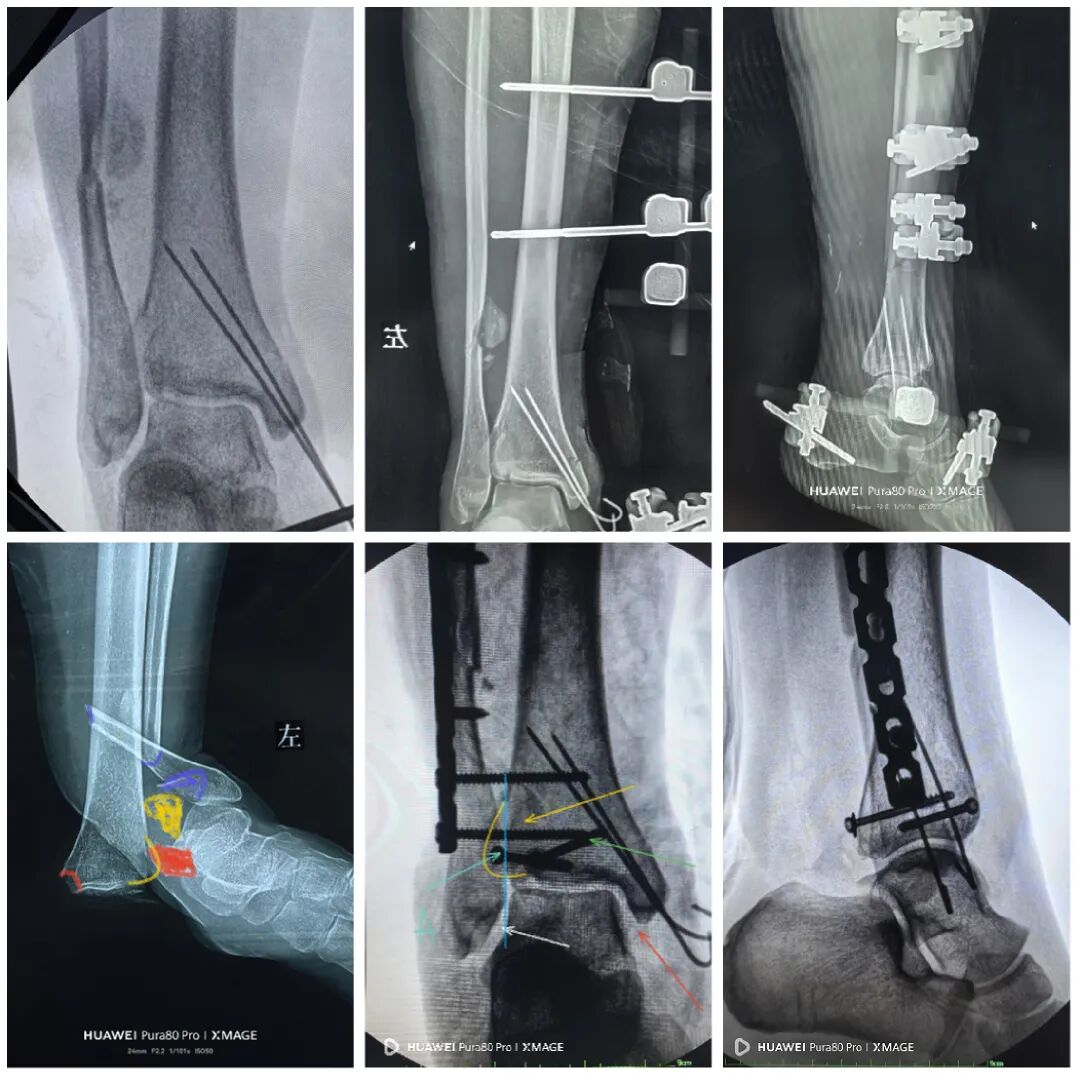

1,前侧小切口,复位Chaput骨块,3.5 mm空心钉垂直骨折线固定

2,腓骨粉碎,恢复长度即可,桥接固定,大蝶骨块用两个nice结捆于钢板

3,复位后踝

最后做下胫腓

两个位置螺钉固定

下胫腓关节复位

内踝间隙恢复

缝合前侧和后外侧切口

取外架

缝合钉道